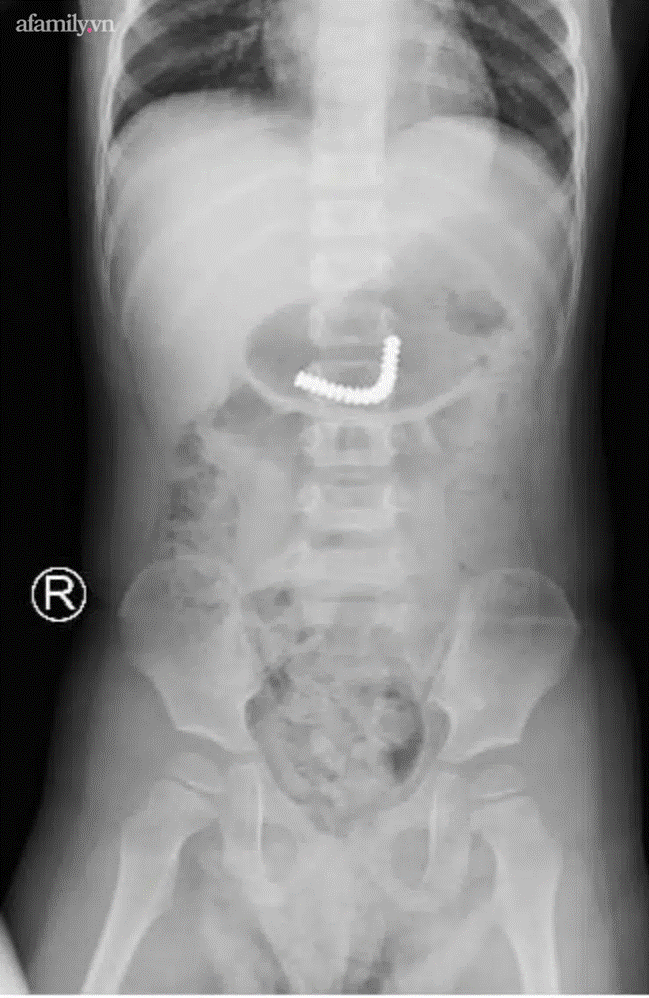

Ảnh chụp phim phát hiện dị vật.

Chụp phim kiểm tra, các bác sĩ thấy dị vật trong dạ dày. Bệnh nhi được đưa đi nội soi tiêu hoá khẩn thì thấy dị vật đã xuống ruột non.